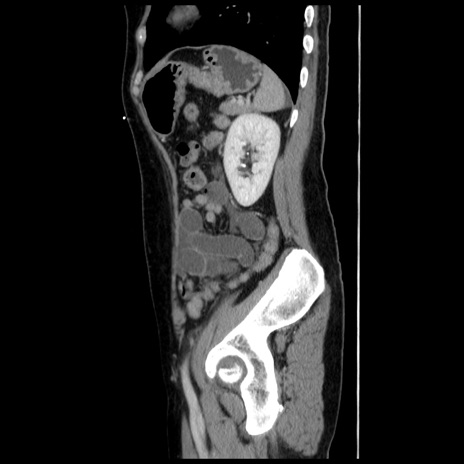

横断像

【症例】 50歳代女性

【主訴】 腹痛

【現病歴】前日生レバーを食べた。今朝に排便あり。 昼前に突然発症の腹痛を生じ、当院救急外来を受診した。

【既往歴】 子宮筋腫にてで子宮全摘後

【身体所見】 意識清明、腹部:平坦、軟、下腹部やや左を中心に圧痛・反跳痛あり、筋性防御あり

【データ】WBC 7800、CRP 0.07